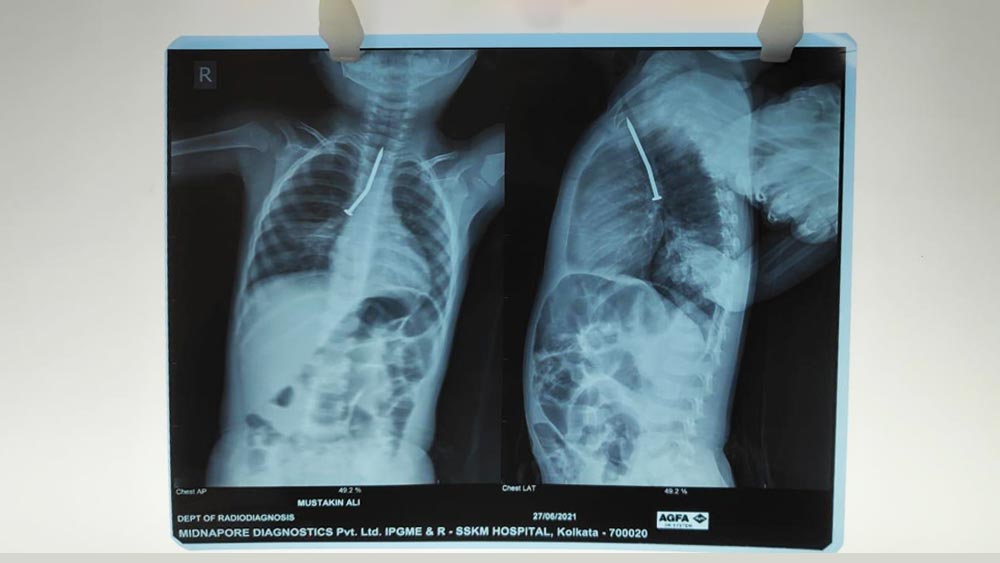

এসএসকেএম সূত্রে খবর, বাচ্চাটির বাড়ি উত্তর দিনাজপুরে। তার শ্বাসনালীর ডান দিকের দেওয়ালে একটি ৬-৭ সেন্টিমিটার লম্বা পেরেক গেঁথেছিল।

খেলতে খেলতে আস্ত পেরেক গিলে ফেলেছিল বছর দুয়েকের ছেলেটি। তার পর থেকে শ্বাসকষ্ট, বমি হওয়ায় ছেলেকে হাসপাতালে নিয়ে গিয়েছিলেন মা। সেখানে প্রাথমিক চিকিৎসার পরেও সুরাহা না মেলায় বাচ্চাটিকে কলকাতার এসএসকেএমে রেফার করা হয়েছিল। রবিবার সকালে ঘণ্টা দুয়েক ধরে অস্ত্রোপচারের পর বাচ্চাটির শ্বাসনালী থেকে পেরেকটিকে বার করেছেন এসএসকেএমের চিকিৎসকেরা।

হাসপাতাল সূত্রে খবর, মুস্তাকিম আলি নামে ওই বাচ্চাটির বাড়ি উত্তর দিনাজপুরের হাতগাছি এলাকায়। তার শ্বাসনালীর ডান দিকের দেওয়ালে একটি ৬-৭ সেন্টিমিটার লম্বা পেরেক গেঁথেছিল। রবিবার সকালে অস্ত্রোপচারের পর সে সুস্থ রয়েছে। এই মুহূর্তে পেডিয়াট্রিক আইসিইউ-তে রয়েছে বাচ্চাটি।

এসএসকেএম কর্তৃপক্ষ জানিয়েছেন, রবিবার সকাল ৭টা থেকে রিজিড ব্রঙ্কোস্কপি পদ্ধতিতে মুস্তাকিমের অস্ত্রোপচার শুরু হয়েছিল। নাক, কান, গলার চিকিৎসা বিভাগের বিভাগীয় প্রধান অরুণাভ সেনগুপ্তের তত্ত্বাবধানে ৪ সদস্যের চিকিৎসক দল এই অস্ত্রোপচার করে। তাতে ছিলেন সন্দীপ্তা মিত্র, মৃদুল জুনেজা, কামরান আহমেদ এবং স্পন্দিতা ঘোষ-সহ ৩ জন অ্যানাস্থেটটিস্ট। চিকিৎসকেরা জানিয়েছেন, পেরেকটি মুস্তাকিমের শ্বাসনালীতে গেঁথে থাকার কারণেই তার বমি ও শ্বাসকষ্ট হচ্ছিল। অস্ত্রোপচার না করা হলে তার খোঁচায় শ্বাসনালী ফুটো পর্যন্ত হয়ে যেতে পারত।